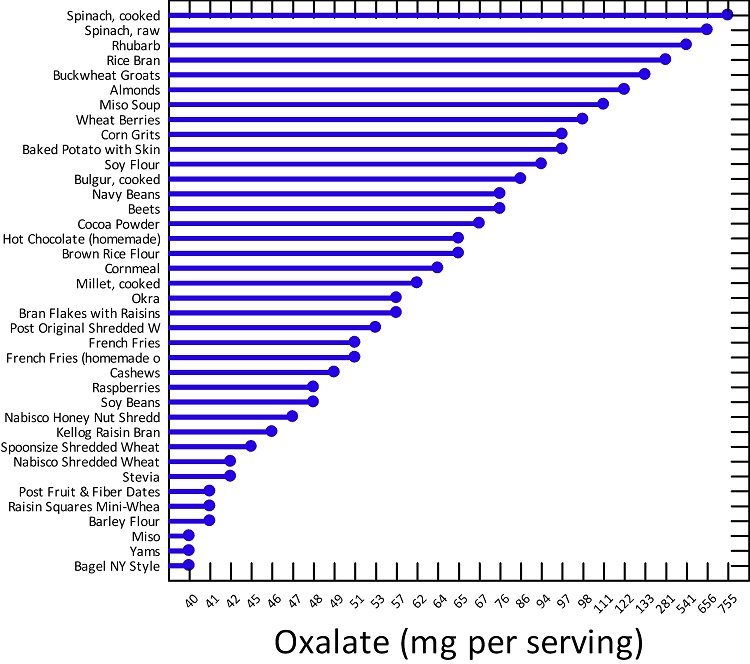

There is a truism in the sociology of occupational knowledge: “If all a doctor has is a hammer, then everything becomes a nail”. All modern medicine relies on overkill dosages of drugs or surgery as the standard of care (Jennifer Daniels, MD, The Lethal Dose, 2013). There are no drugs or surgery that can alleviate the symptoms of poisoning from a natural pesticide found in plant foods but also produced in the liver. With this professional void, treating oxalosis has mainly been left to nutritionists. So, if you ask a nutritionist about oxalates, you will get a predictable answer to reduce oxalates in your diet. This is insufficient because most oxalates are produced by poor metabolism in the liver. Oxalate is a natural pesticide found in plant foods, but also is internally produced mainly from fungus and vitamin C (see How Oxalates Ruin Your Health). Oxalosis manifests as a syndrome of three main symptoms: oxalate crystals in tissues and kidney; histamine, mucous attack in nasal passages; and pseudo-gout mainly from acidity and eating cooked meat.

First, I learned that calcium is needed as a co-valent chemical binder to oxalate before meals to eliminate oxalate through the bowel or oxalic acid through with urine through the kidney. Secondly, I learned that plant foods like spinach, almonds, chocolate, and soy and were loaded with toxic levels of oxalates, a natural pesticide that protects plants from insects, worms, and herbivores. I also learned that high doses of synthetic Vitamin D (10,000 mg/day as a steroid) without Vitamin K2, could also lead to kidney stones and oxalosis. An iron deficiency may come into the picture as discussed below.